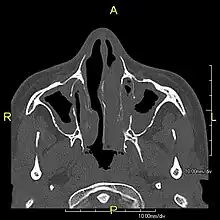

Diagnosis

Several diagnostic tests for this condition have been proposed.[5] These include nasal nitric oxide levels as a screening test, light microscopy of biopsies for ciliary beat pattern and frequency and electron microscopic examination of dynein arms, as the definite diagnosis method. Genetic testing has also been proposed but this is difficult given that there are multiple genes involved.[6]